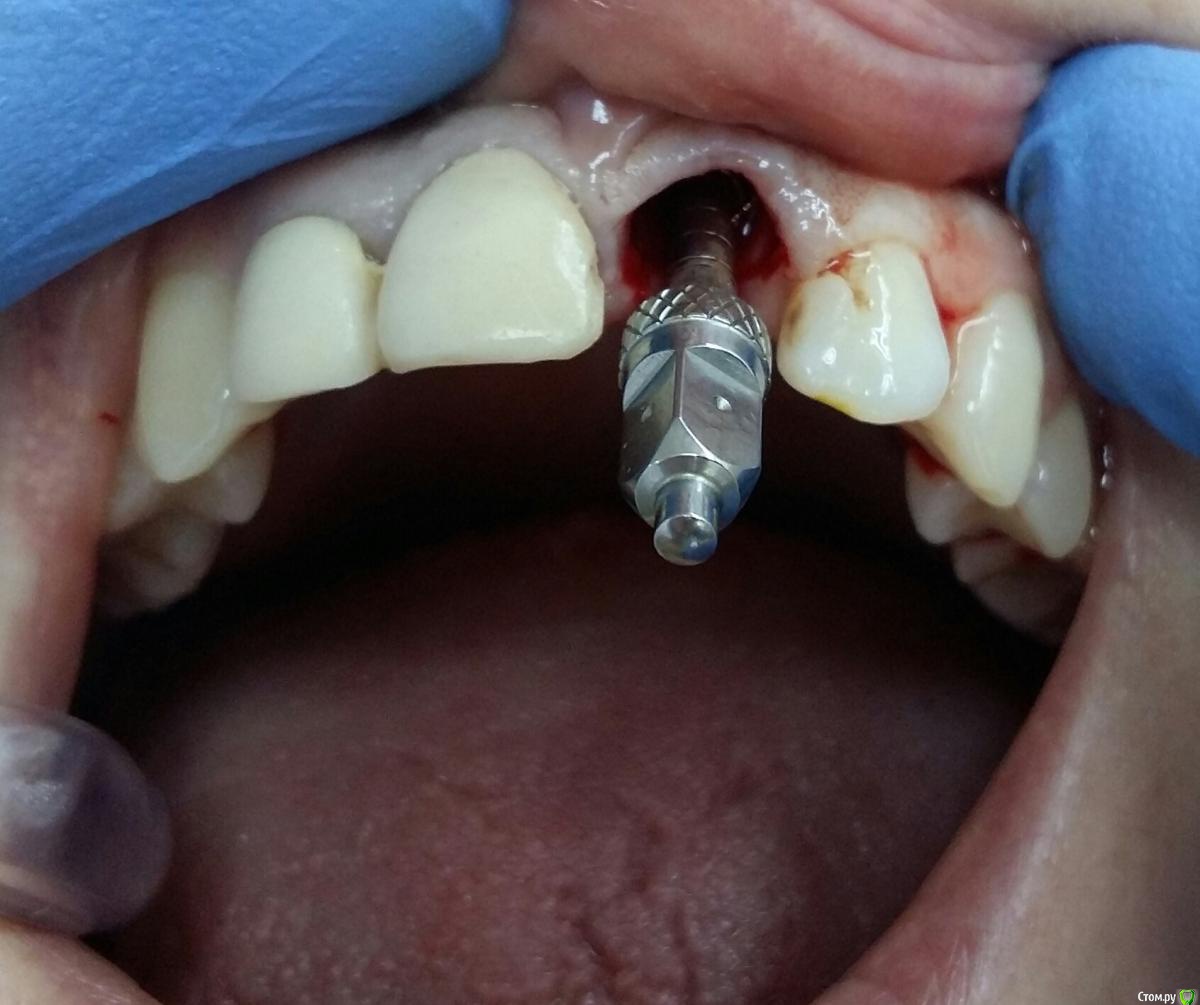

Kostoprav Опубликовано 8 ноября, 2017 Поделиться Опубликовано 8 ноября, 2017 заранее извиняюсь за качество фотографийдумал сделать все в один этап но торка ожидаемого не получил, поэтому пришлось накрыть винт випом.(материал osteobiol putyy) мне он очень понравиля ,удобный в работе. 17 Ссылка на комментарий

Kostoprav Опубликовано 8 ноября, 2017 Автор Поделиться Опубликовано 8 ноября, 2017 Торк был не достаточный для временной реставрации. Около 20. Я не рискнул.Срезы если найду выложу, хотя там ситуация стандартная ничего из ряда вон выходящего Ссылка на комментарий